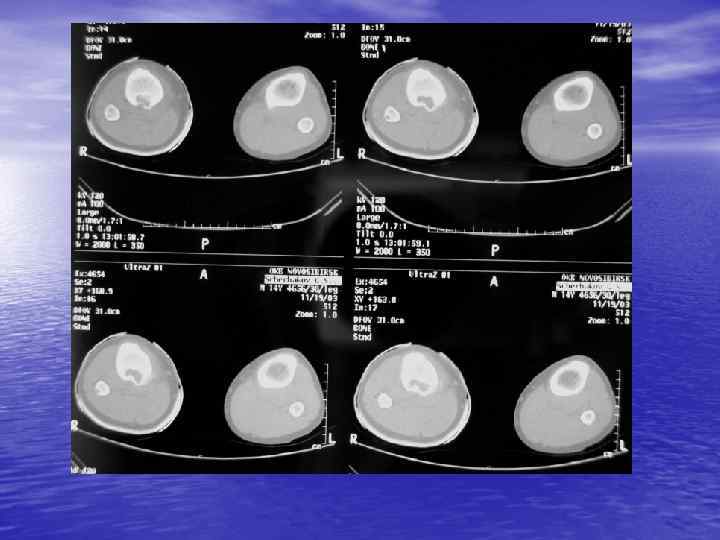

Денситометрический анализ Определение основных видов патологических образований: - обызвествленных - мягкотканных - жидкостных - жиросодержащих - воздухсодержащих

Денситометрия